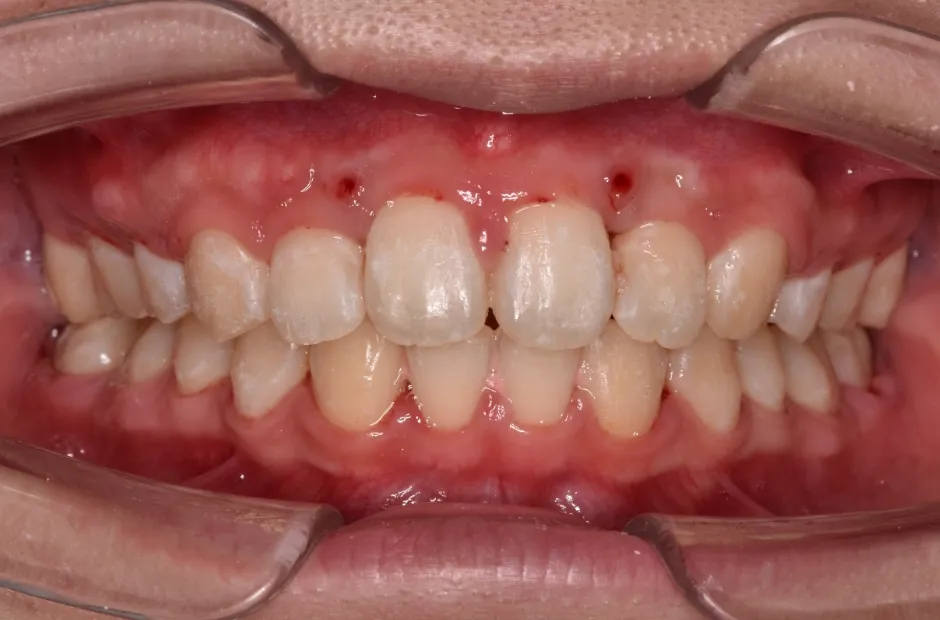

すきっ歯

| 診断名・主訴 | すきっ歯 |

|---|---|

| 年齢・性別 | 22歳・女性 |

| 治療期間・回数 | 2年半 30回 |

| 治療に用いた主な装置 | アンカー |

| 抜歯部位 | なし |

| 治療費 | 100万円(税抜) |

| リスク・副作用 | 装置による違和感・疼痛・歯肉退縮・歯根吸収・虫歯のリスクなど |

治療後